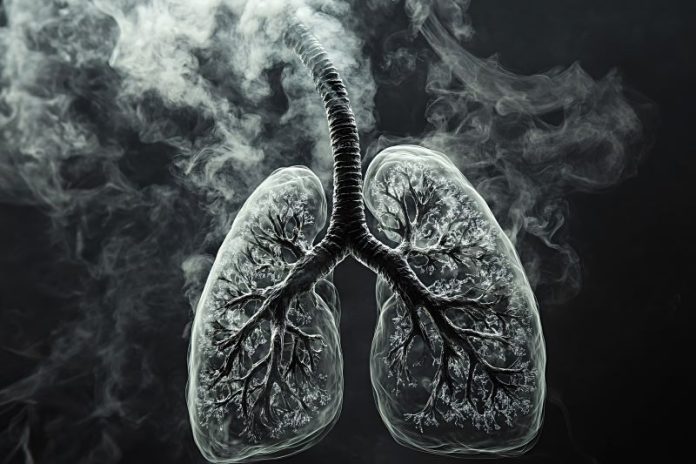

臺北市政府衛生局李碧慧副局長指出,全球已有超過7萬份研究報告證實,菸品對健康的危害極為嚴重。吸菸不僅是「不好的習慣」,更是一種「不健康的行為」。為響應國際行動,衛生局特結合教育局、董氏基金會即日起至113年11月15日止辦理「認清菸商真面目」答題抽獎活動,不僅能提升菸害防制知能,還有機會抽中iPad和郵局現金禮券,歡迎踴躍參加!